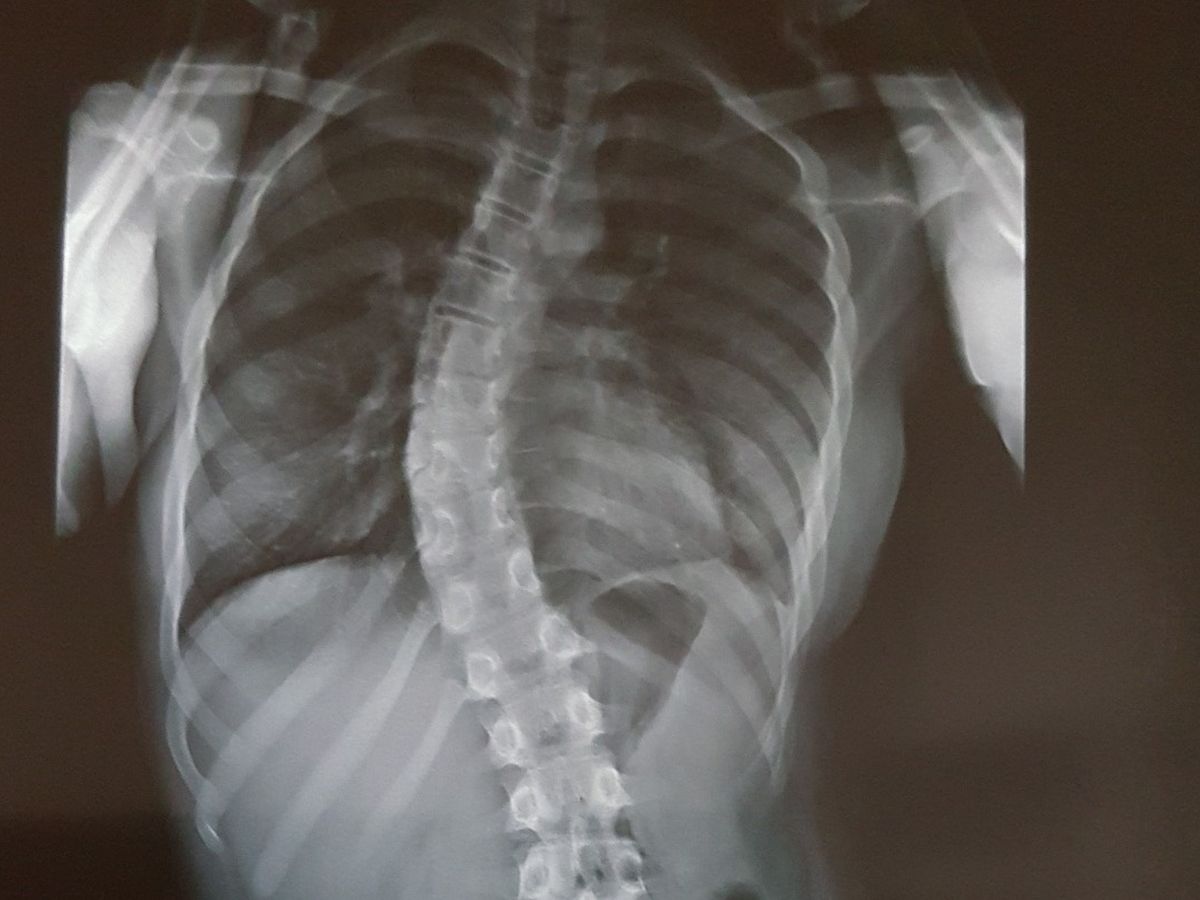

My daughter, Kayra, has been diagnosed with scoliosis last year. The curve was initially measured as 39 degrees. We have started treatment in the Royal Children’s Hospital in Melbourne immediately. As the first treatment strategy, the doctors recommended to have a body brace for her to wear as close to 24 hours/day as possible. Brace apparently is not a treatment strategy but a preventative one, for an attempt to try to make sure the curve doesn’t bend any further.

Unfortunately, our follow up check-up indicated that the curve was actually 49 degrees and now progressed to 52 degrees, i.e. bracing hasn’t helped. We were advised that anything greater than 50 degrees will most likely require an operation to correct it. The common type is to fuse the bones during early adulthood but this will restrict her movements for the rest of her life. Exploring all other treatment options, we have found a new treatment approach called “Vertebral Body Tethering (VBT)” which is a new cutting edge fusion-less technique used by only a handful of skilled surgeons across the world to treat scoliosis. It requires titanium bone screws to be anchored to the front of each vertebral bone within the curved area, and a flexible cord (the tether) to be attached to each screw and tensioned to achieve the desired degree of spine straightening. This technique is less invasive, however, it is time-sensitive. It can only be done to those patients who haven’t completed their growth as this method takes advantage of future growth in which the tethered side of the spine grows less than the non-tethered side.

Kayra is nearly about to complete her growth cycle according to her x-rays. Hence the clock is ticking for us if we have a chance to give her a better life for the future. As a parent, we would like to try every avenue as she will benefit from this surgery if operated as soon as possible.